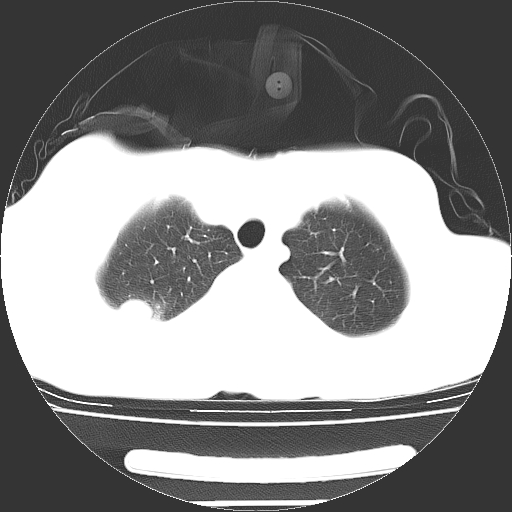

以下是引用dyqct在2008-4-29 8:43:00的发言:[br][br] 支持右侧胸腔包裹性积血。闭式引流管是不是插的太深了?

以下是引用zjzjr在2008-4-29 14:11:00的发言:[br]支持右侧胸腔包裹性积血。闭式引流管是不是插的太深了?胸腔引流,引流管快进入纵隔了.